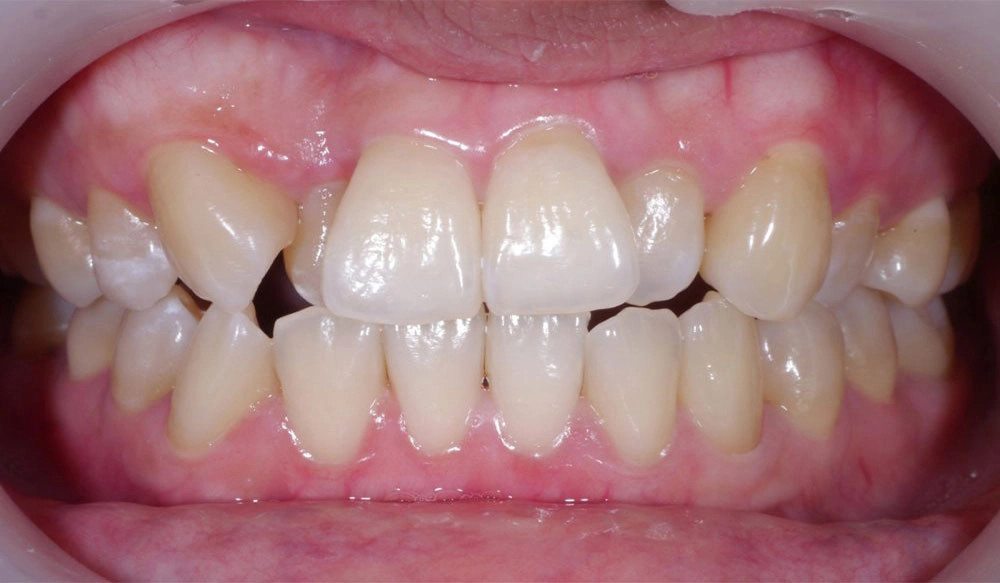

Midline Discrepancy

Midline discrepancy is the condition in which there is a misalignment of the midsagittal line of maxillary and mandibular arches respectively and/or relative to the facial midline.

Patient Information:

Age: 28

Gender: Female

Invisalign Treatment Option: Invisalign Comprehensive

Total Treatment Time:

16 months